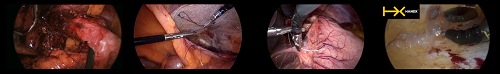

與其他腹腔鏡系統(tǒng)一樣,Human Xtensions的應(yīng)用范圍可用于各種腹部外科手術(shù),如胃腸道、疝氣、結(jié)腸直腸、胸腔等。而該公司將這種控制腹腔工具的新方法稱為“endo-robotic surgery”。

且因四個(gè)小型工具直徑都是5毫米,對(duì)此,也使得它們的侵入性更小,留下的皮膚痕跡也更小。在臨床使用中可見在應(yīng)用時(shí)效果明顯,對(duì)患者損害較少。